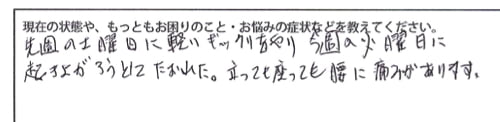

今までの治療履歴はこんな感じでした。

病院や整形外科、整骨院・整骨院・マッサージなど色々通われていて

ぎっくり腰は、あまりにも痛みが引かないので検査をしてみましたが

骨やその他には異常なしとのことでした。